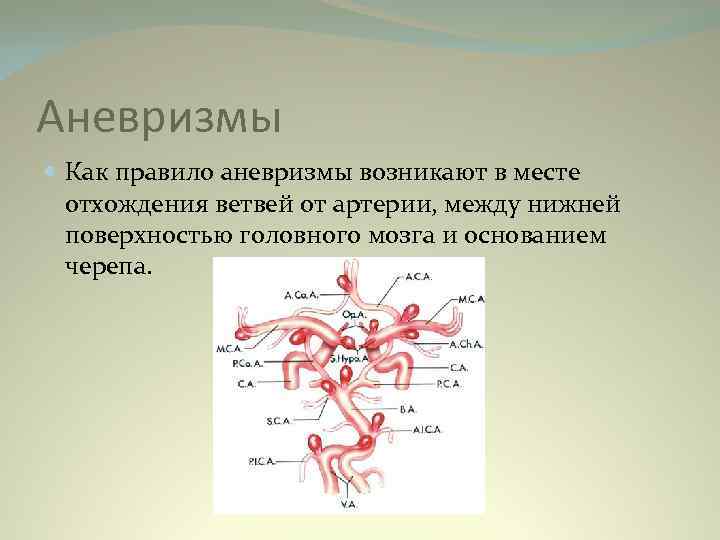

Снимки и иллюстрации микроаневризм сосудов головного мозга